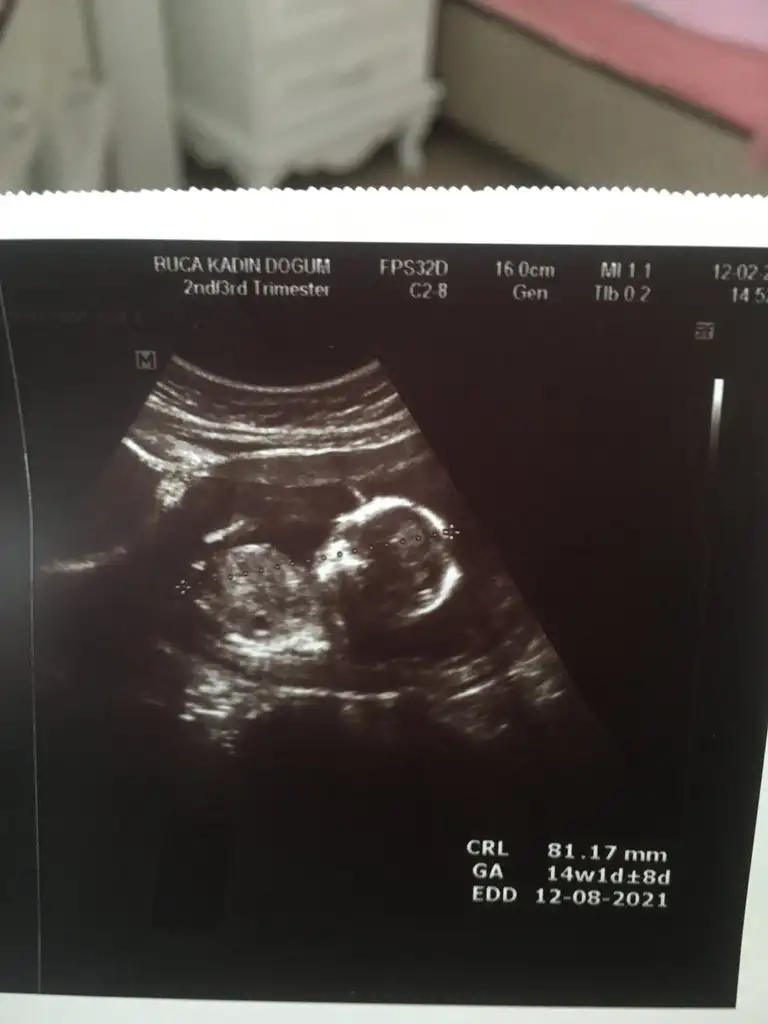

Buradaki hanımların nub teorisine göre kız gibiEki Görüntüle 2764421 Eki Görüntüle 2764422 Eki Görüntüle 2764423 Tahminde bulunur musunuz arkadaşlar